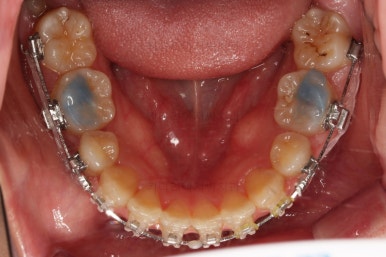

마찬가지로 부산연산동교정치과 초진 시 입안의 모습입니다.

눈에 띄는 것은 윗니 안쪽 치아 하나가 아예 입천장쪽으로 나서 매우 삐뚤어요.

저렇게 삼각혁으로 배치되어 있는 치아는 셋 중 하나는 꼭 썩어요.

셋 사이에 음식물이 잘 끼고 양치가 힘들기 때문이죠.

아래 앞니도 삐뚤한 편이었고 아래 앞니가 불쑥 위로 올라와 있어서 이를 악 다물면 위아래 앞니가 많이 겹치는 "과개교합" 패턴이 나타나요.

윗니가 전반적으로 아랫니보다 앞에 나와 있어서 2급 부정교합에 윗니만 튀어나온 양상이고 이 때문에 윗니 앞니가 다치고 부러졌따가 떼운 흔적이 보이네요.

환자분이 선택하신 장치는 엠파워 클리어라고 하는 자가결찰 세라믹 장치에요.

흔히들 클리피씨라고 많이 알고 계신 장치도 자가결찰 세라믹 장치의 한 종류에요.

제조사가 일본(클리피)이냐 미국(엠파워)이냐의 차이일 뿐이죠.